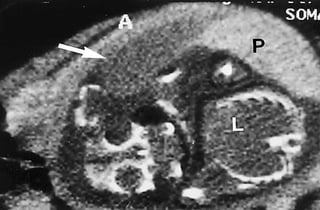

USG PICTURES OF ABDOMEN OF

A PREGNANT WOMEN WITH

BLUNT TRAUMA OF ABDOMEN

PHOTOS OF CT EVALUATION OF

PREGNANT WOMAN WITH TRAUMA– CT

SCANS DONE AS A PART OF INVESTIGATIONS

DONE IN EMERGENCY --- MATERNAL HEAD

AND ABDOMEN AS PER NEED OF INDIVIDUAL

CASE ---WITHOUT FEAR OF X RAYS

EXPOSURE TO FETUS IN UTERO